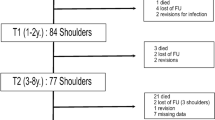

Favard L, Lautmann S, Sirveaux F. Hemi arthroplasty versus reverse arthroplasty in the treatment of osteoarthritis with massive rotator cuff tear. In: Walch G, Boileau P, Mole D, eds. 2000 Shoulder Prostheses: Two to Ten Year Follow-up. Montpellier, France: Sauramps Medical; 2001:261–268.

Guery J, Favard L, Sirveaux F, Oudet D, Mole D, Walch G. Reverse total shoulder arthroplasty: survivorship analysis of eighty replacements followed for five to ten years. J Bone Joint Surg Am. 2006;88:1742–1747.